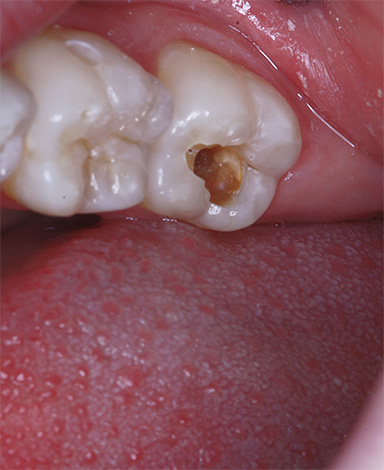

Se houver um orifício no esmalte (cavidade), definitivamente não será possível curar um dente sem obtê-lo. Em muitos casos, essas lesões de cárie que só podem ser tratadas por um dentista se apresentam como manchas marrons ou pretas distintas.

Isso é especialmente verdadeiro para fissuras, onde esses pontos às vezes podem ser muito pequenos e não se incomodam com nada, e é por isso que muitos não os percebem como um problema sério. Enquanto isso, a área da lesão sob essa mancha já pode penetrar profundamente na dentina.

Devido ao pequeno tamanho das áreas escuras na área da fissura, muitos acreditam que esses pontos podem simplesmente ser clareados ou lixados em casa, e a cárie dentária como se isso fosse curado. De fato, essa mancha é apenas um sinal de que a cárie não pode ser curada sem preenchimento.